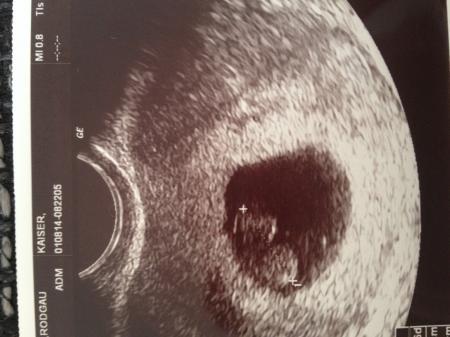

Schaut mal, das ist das letzte Bild von unserem Krümel (wurd Freitag gemacht).... Ich möchte es euch nicht vorenthalten...! *wir lieben Dich kleiner Stern*

Sehr schönes Bild und schöne Erinnerung an euer Sternchen!! Weis wie schwer es ist, ein absolutes Wunschkind zu verlieren. Und ich bewundere sehr deine Stärke! Ich wünsche euch alles, alles Liebe und Gute weiterhin.

Ein schönes Bildchen von eurem Stern.

Du bist spitze nessa! Daumen hoch fur deine positive Einstellung! Lg ps: süßes bild. Es wird immer eine Erinnerung sein für euch an euer Sternchen das nun über euch wacht..